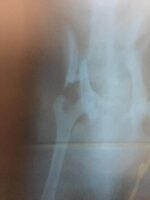

Desta vez, dois cães foram atropelados, sendo que um deles fraturou a bacia e o outro a pata. No dia 23 de janeiro, a voluntária cobrou providências e denunciou que uma gatinha foi atropelada e não resistiu aos ferimentos Veja: Jovem da ONG Adota Patos denuncia que animais são constantemente atropelados na Rua Semeão Gentil, no Bivar Olinto. Ela pede providências.

Na Rua Semeão Gentil, no Bivar Olinto, não aguentamos mais ver animais sendo atropelados. Vários já vieram a óbito, e nesta última segunda-feira, 29/03, atropelaram dois cães, onde um quebrou a bacia e o outro fraturou a pata.